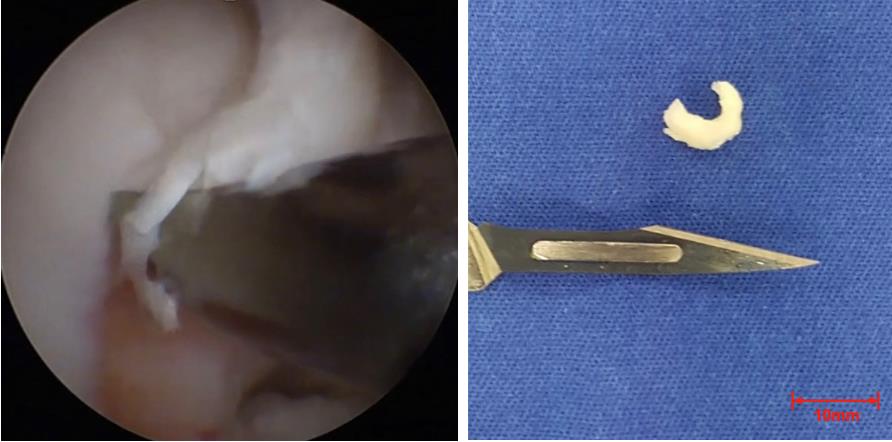

2. Following arthroscopic inspection, extract a 5–10 mm full-thickness cartilage fragment from a non-weight-bearing area on the lateral edge of the trochlea or intercondylar notch using a specialized arthroscopic gouge (Figure 1).

Figure 1. Cartilage obtained by arthroscopic surgery. (Left) Arthroscopic image of the surgery at the moment of cartilage collection. (Right) Cartilage fragment.